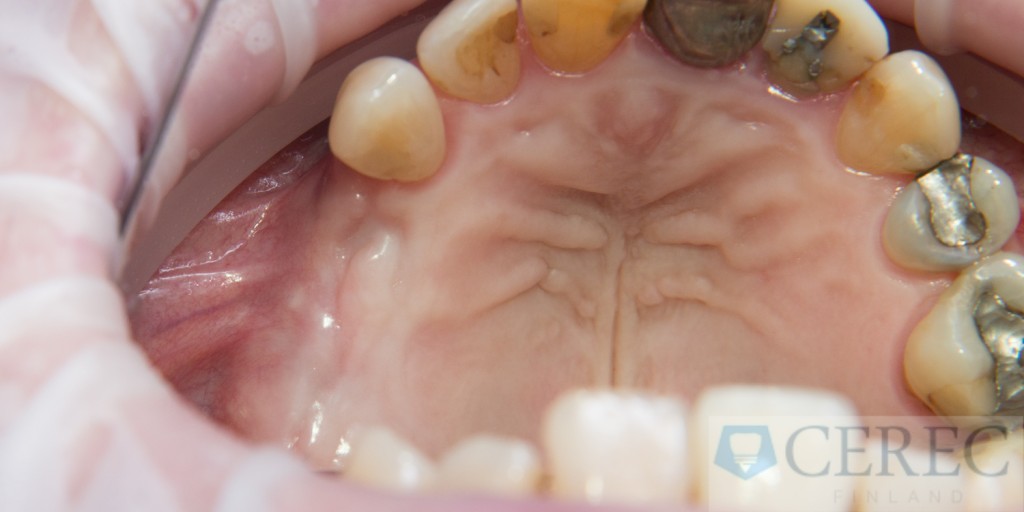

Potilaalta puuttui ylhäältä oikealta kaikki takahampaat.

Päädyimme tekemään yksittäisiä implantteja täysin ohjatusti 3d suunnitelman perusteella. Tällä uudella lopullinen hammas suunnitellaan ennen implanttiruuvin asentamista. Tällöin voidaan varmistaa, että implantin sijainti ja syvyys tulee olemaan ideaalinen, niin että lopullisesta rakenteesta tulee hyvin samankaltainen kun omasta hampaasta.

Perinteisesti ohjattu implantointi on tuonut implanttihoitoon lisämaksuja jopa 50%. Cerec mahdollistaa ohjatut implantoinnit niin että potilaalle ei synny huomattavia määriä ylimääärisiä kustannuksia. Tällöin jokainen hammasimplantti voidaan asettaa ohjatusti ja saada implantin ennusteesta niin hyvä että se voi kestää läpi elämän.  Ideaalinen implantin sijanti välittyy hygienisempina ja esteettisempinä rakenteina.

Alkuperäinen tilanne ja hampaan puutosalueet: